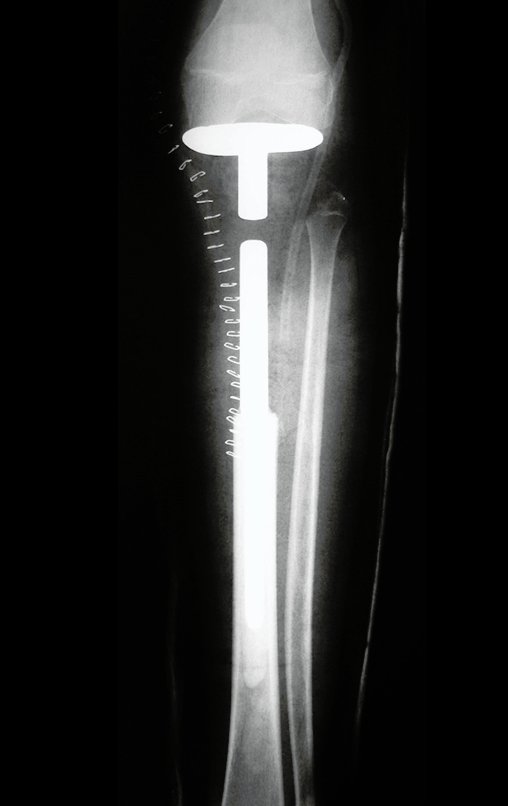

Osteosarcoma tibial: prótesis parcial y ligamentoplastia

Prótesis Parcial de Tibia. Paciente femenina, 12 años, fecha de nacimiento 18 de marzo de 2003, comenzó en abril con dolor y cojera, consultó en varios centros y fue tratada con analgésicos.

Ingresó en el hospital en mayo y se sometió a una biopsia por punción. El informe anatomopatológico indicó osteosarcoma central convencional localizado, con cultivos negativos. Se le realizó estadificación con TC de tórax, gammagrafía ósea de todo el cuerpo y resonancia magnética del miembro inferior derecho. Se le realizaron tres ciclos de quimioterapia neoadyuvante con Platino y Doxorrubicina, con buena respuesta.